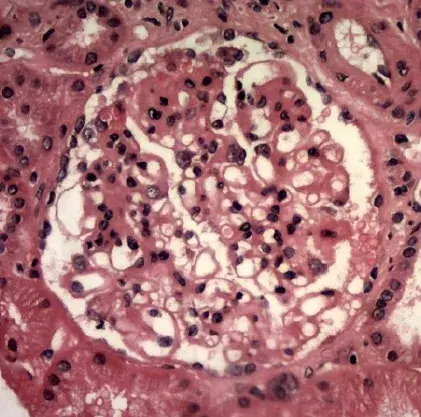

glomerulopatias

nefrite lupica